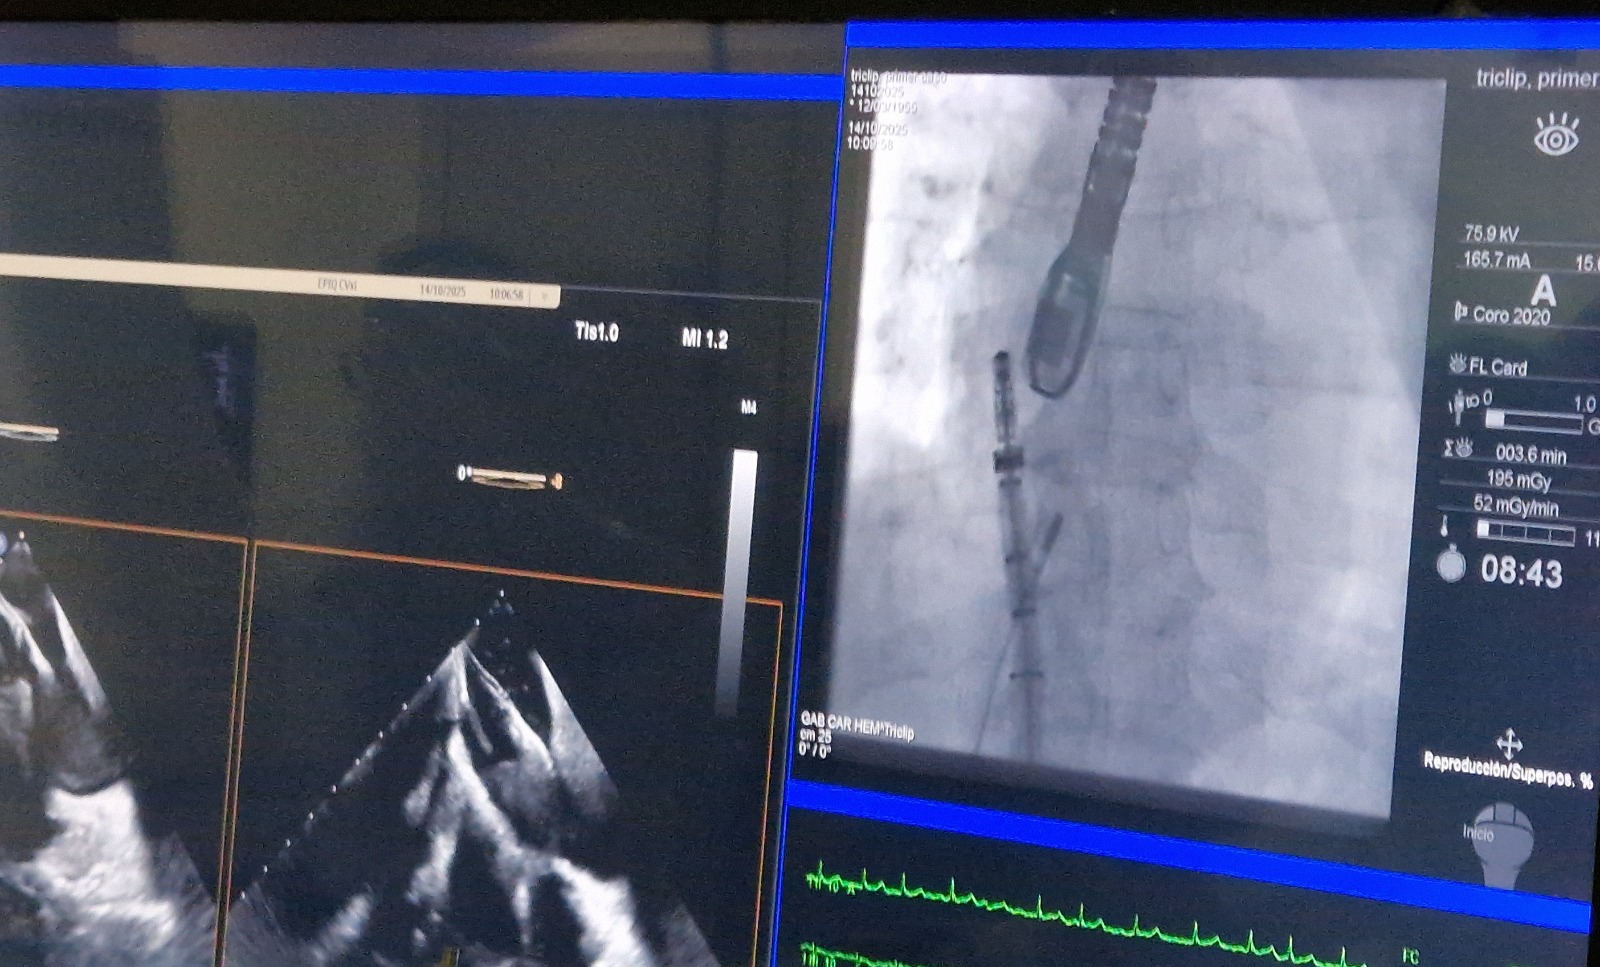

Ayer, en el centro sanitario se realizó la primera intervención guiada por esta sonda, que supone un importante elemento de apoyo para que los médicos puedan realizar procedimientos coronarios mínimamente invasivos, con mayor precisión y seguridad, que reducen las complicaciones.

La primera paciente intervenida con este sistema fue una mujer de 75 años, a la que se le practicó una reparación percutánea de la válvula tricúspide mediante la fijación de dos clips que unen los bordes de los velos, mejorando el cierre y aliviando los síntomas de insuficiencia cardíaca.

La intervención se completó sin complicaciones y la paciente evoluciona favorablemente. Posteriormente se hicieron otras dos intervenciones similares con los mismos resultados y a lo largo de estos días, el HUCA realizará ocho procedimientos diferentes con esta sonda. De esta forma, se convertirá en uno de los hospitales de Europa con más experiencia en su uso, que, a partir de 2026, se extenderá por otros hospitales de España y Portugal.

Avanzas también explicó que, por razones de seguridad, en estos primeros casos se combinan la imagen de la nueva sonda junto y la de la sonda transesofágica convencional, que se introduce a través de la boca, aunque pronto “vamos a poder hacer este tipo de intervenciones sin que sea necesario introducir sondas por el esófago, lo que simplifica el procedimiento, mejora la recuperación y reduce riesgos”.